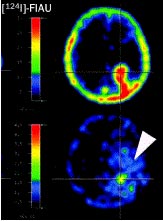

- Algunos tipos de Cáncer.Imágenes de expresión génica en modelos experimentales.

I-124 FIAU, marcador de expresión del Virus Herpes simple tipo 1, en un paciente con glioblastoma, en evaluación de terapia con Ganciclovir.